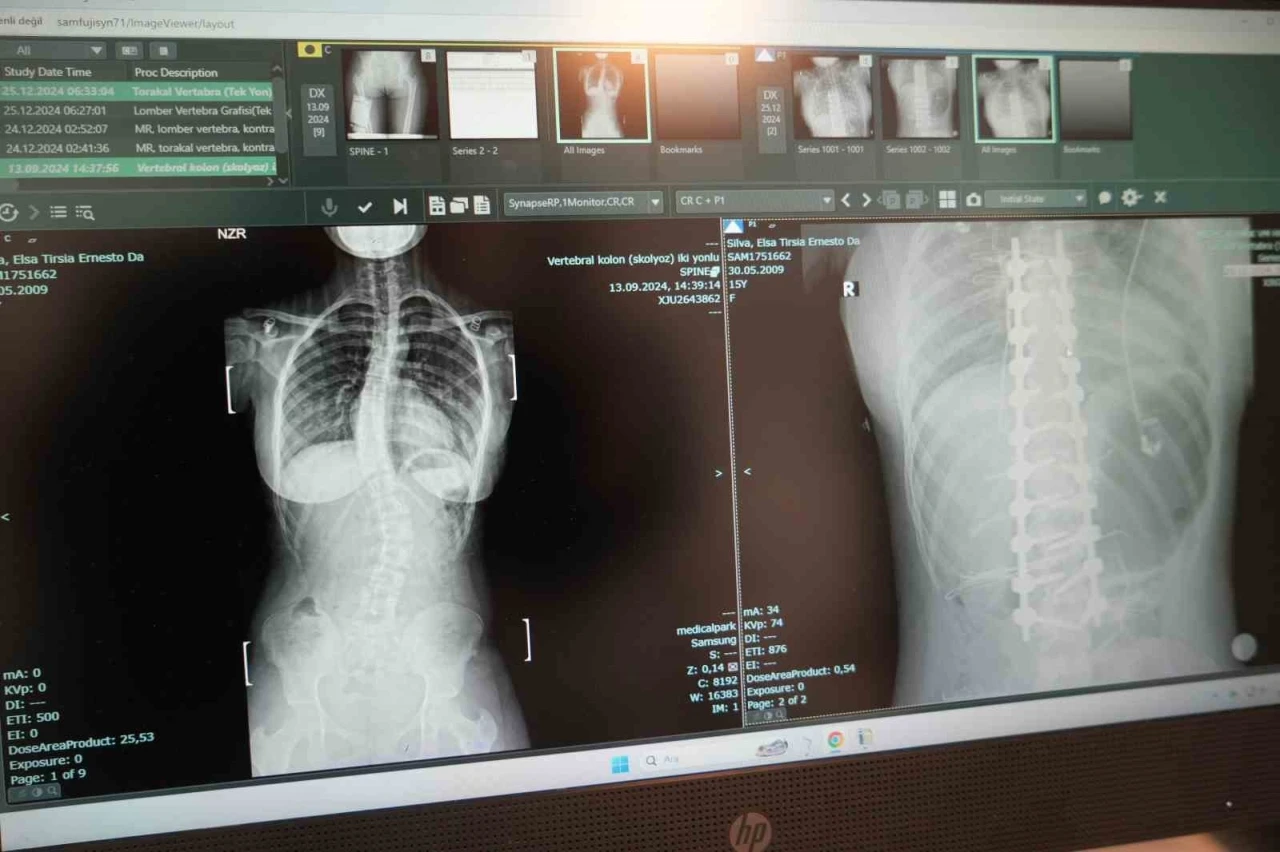

Omurgasında 45 derece eğrilik bulunan skolyoz hastası 15 yaşındaki Elsa Silva, Angola’dan Samsun’a gelerek burada yapılan ameliyatla şifa buldu.

Hastanın ameliyatını gerçekleştiren Ortopedi ve Travmatoloji Uzm. Prof. Dr. Turgut Nedim Karaismailoğlu, "Hastamızda skolyoz mevcuttu. 2 ay önce bize geldi. Angola’da yaşıyorlar. Geldiğinde 45 derece bel eğriliği mevcuttu. Yaşı 15’ti ve bu yaşta ameliyat olması gerekiyordu. Hasta, ameliyattan sonra ikinci gün ayağa kaldırıldı. Üçüncü günde taburcu edildi. 15. günde dikişleri alındı. Bu ameliyatlar ağır ve dikkat isteyen ameliyatlardır. Bu konuda Türkiye’de son dönemde çalışan uzman sayısı arttı. Samsun’da bu imkan olduğu için çevre ülkelerden gelen hasta sayısında artış mevcut. Biz de onlara elimizden geldiğince cevap vermeye çalışıyoruz" dedi.